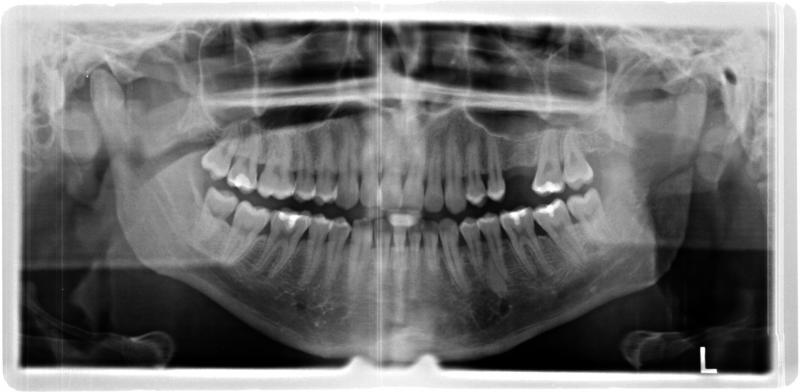

ich habe seit Jahren mit Nasennebenhöhlenentzündungen zu kämpfen da ich auch Allergiker bin. Nun war ich wegen Zahnschmerzen im Oberkiefer beim Zahnarzt. Der konnte oder wollte nichts feststellen trotz Röntgen. Auf die Frage ob Zahnwurzeln in die Kieferhöhle ragen sagt er mir das meine Oberkieferzähne in die Kieferhöhle ragen und hat es harmlos geredet. Ich glaube das ich seit Jahren eine chronische Kieferhöhlenentzündung habe die nicht entdeckt wurde, da ich einige Symptome habe die darauf deuten. Durch Ihr Youtube Video über Kieferhöhlenentzündung bin ich darauf gekommen deshalb dachte ich mir ich frage Sie hier im Forum. Vielleicht können Sie etwas anhand meiner Röntgenbilder die ich habe erkennen ob ich richtig liege mit meiner Vermutung. Ich bedanke mich im Vorfeld.

ich bin mit meinem Latein am ende kein HNO oder Zahnarzt hilft mir richtig bzw behandelt mich richtig um die Ursachen meiner Beschwerden herauszufinden. Ich hatte damals große Probleme mit meinen Zähnen Karies , Zahnfleischentzündungen usw. Mein Hauptproblem ist das es aus meiner Nase faulig riecht und da denke ich das es definitiv mit den Zähnen zu tun hat. Alle zwei Monate eine Sinusitis kann nicht normal sein. Sekretstau es fließt nicht ab und hängt Rachen fest. Ich muss dauernd Sinupret Extract und Soledum Forte nehmen um es erträglich zu machen , aber ganz weg geht es nicht. Ich habe auch eine Schiefe Nasenscheidewand und Polypen benutze Syntaris Anti Allergisches Nasenspray und nehme Levocetirizin Allergie Tabletten täglich. Ich vermute bzw denke wirklich das ich eine chronische Kieferhöhlenentzündung habe. Ich habe nächste Woche Mittwoch einen Termin bei einem neuen Zahnarzt und lasse mir die Röntgenbilder geben um sie Ihnen hier im Forum zu zeigen. Ich lasse mir lieber diese Zähne ziehen und riskiere es zahnlos zu werden anstatt das nichts versucht wird ich hoffe Sie können meine Verzweiflung nachvollziehen.

Danke für Ihre Zeit und das Video, vielleicht haben Sie Recht mit weniger ist mehr , aber dennoch bin ich davon überzeugt das meine Sinusitis durch die Oberkieferzähne bzw durch eine jahrelange chronische Kieferhöhlenentzündung ausgelöst wird da nach jede mit Sinupret Extract behandelte akute Sinusitis nach 1-2 Wochen schon die nächste ausgelöst wird das ist nicht normal. Wasser trinke ich bis zu zwei Liter am Tag mal mehr mal weniger.